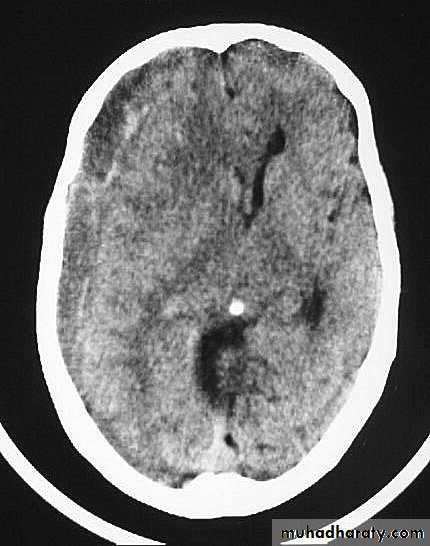

c. Intracerebral Haematoma

This is the least common of traumatic haematoma.

They are due to areas of traumatic contusion coalescing into a contusional haematoma.

Disrupted cerebral tissue release thromboplastins that potentiate haemorrhage.

CT scan: appear as hyperdence lesions with associated mass effect and midline shift.

Large intracerebral haematomas should be evacuated unless the patient’s neurological state is improving.

Small inracerebral haematomas may not require removal, but be aware that they can expand.